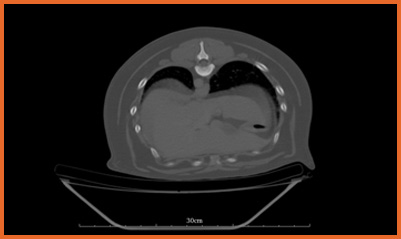

我們提供留院服務並擁有相應的治療設施,亦是小數備有CT電腦掃描及MRI磁力共振等大型醫療儀器的診所及醫院。